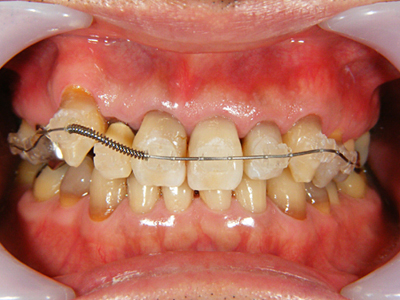

9. 矯正終了前正面

矯正開始前と比較してだいぶ1,3番間が開離して3番の八重歯が改善されています。3番の歯肉辺縁も向上してきています。将来セルフケアしやすいように注意しています。

11. 仮歯仮着時正面

とりあえず歯列は改善しました。審美的なことも重要ですが、やはり衛生面からの環境は向上したものと考えます。仮歯で保定を兼ねています。この写真では右上2,4番を仮歯としていますが1番も補綴予定です。